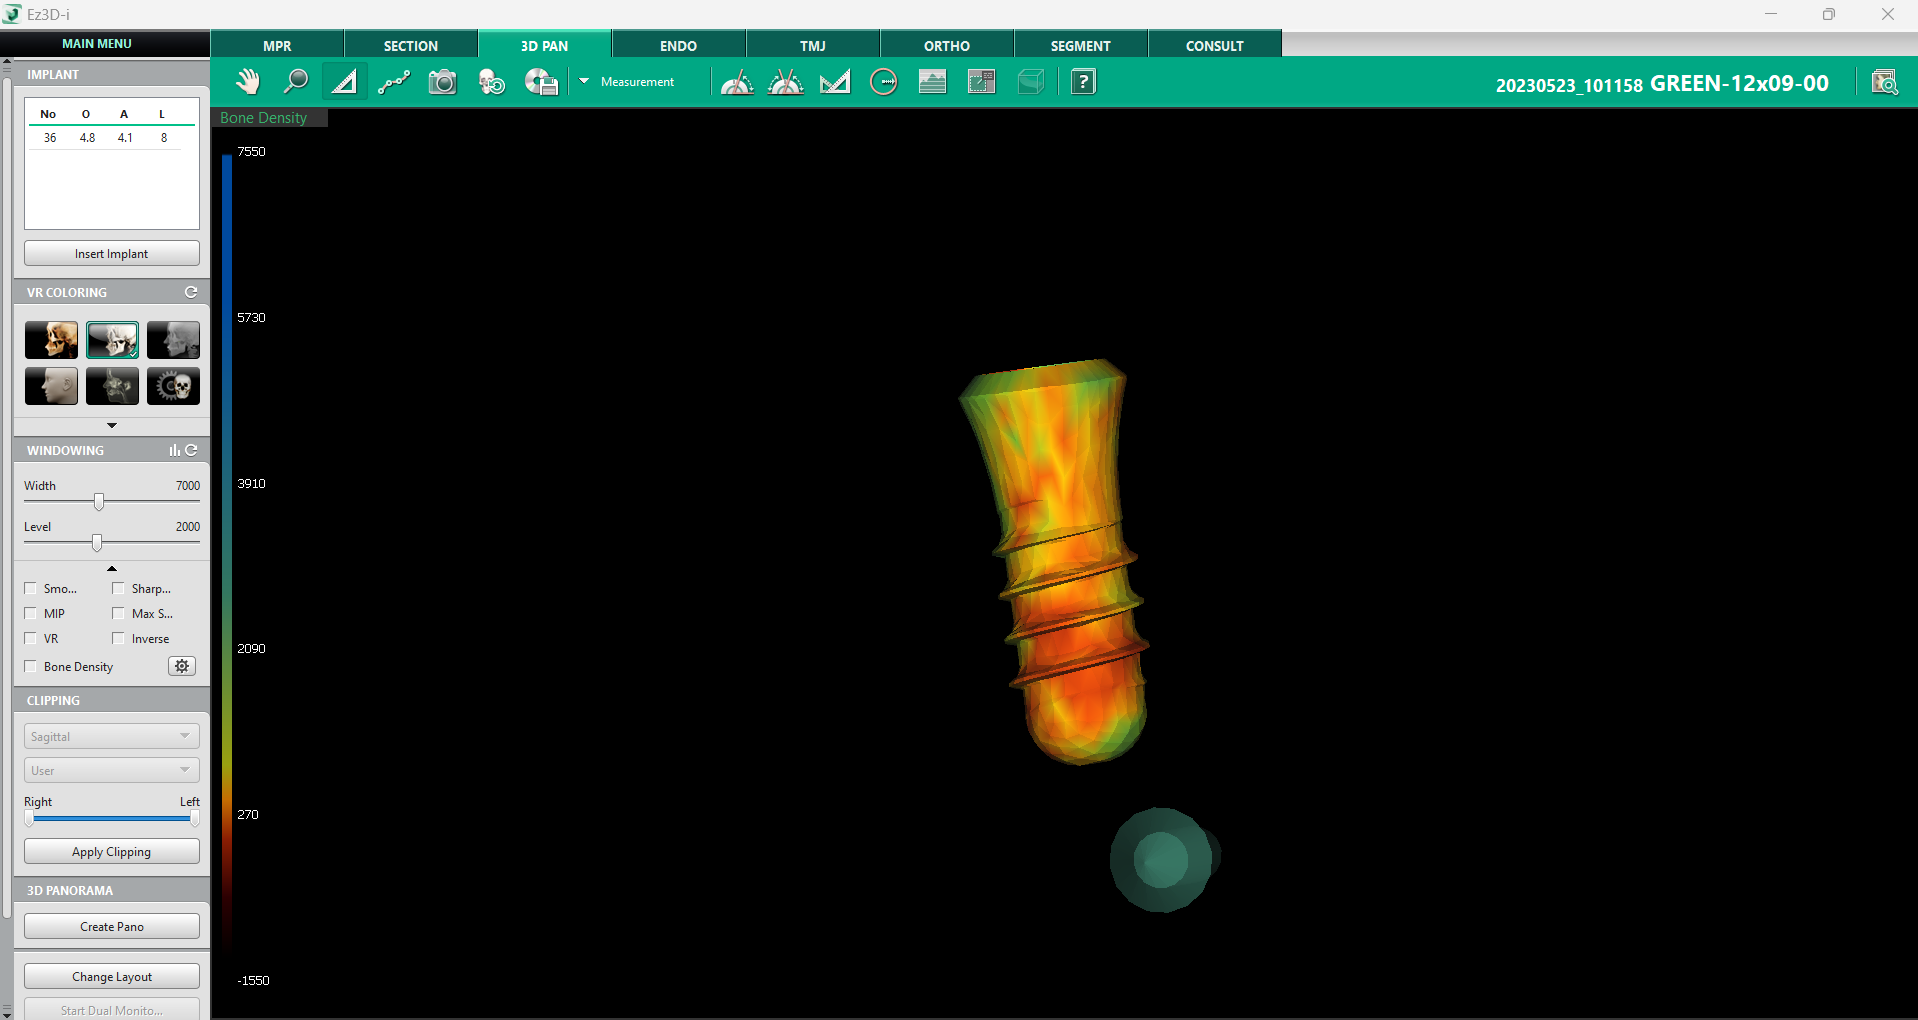

b. Densitatea osoasă a implantului

O evaluare corectă a densității osoase este esențială pentru succesul unui implant dentar. Deși am discutat în acest articolul despre numeroasele instrumentele dedicate analizării densității osoase, acest instrument specific oferă o verificare finală a compatibilității implantului cu osul în care urmează să fie plasat.

Disponibil în tab-ul 3D Pan, instrumentul poate fi activat prin selectarea opțiunii „Change Layout” din colțul stâng inferior al ecranului și alegerea unei configurații care include fereastra „Implant Bone Density”.

După selectarea implantului dorit printr-un click stânga, software-ul va genera automat un model grafic al acestuia, suprapus cu o reprezentare coloristică a densității osoase, conform scalei D1 – D5. Această reprezentare vizuală permite medicului să evalueze în detaliu structura osoasă din jurul implantului, identificând eventualele zone cu densitate scăzută care ar putea necesita proceduri suplimentare, cum ar fi augmentarea osoasă. Modelul poate fi rotit și analizat din orice unghi, oferind o perspectivă completă asupra viabilității implantului.